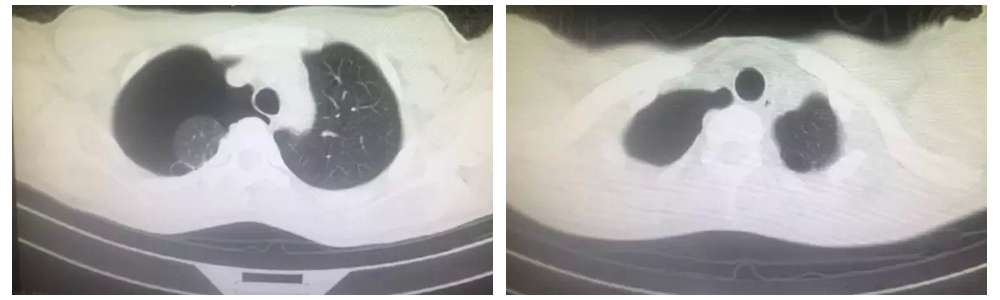

患者周某,是一名高三学生,因胸痛气促入院。查胸CT显示右侧气胸闭式引流术后,右肺被压缩约60%,双上肺尖多发肺大疱。经详问病史,患者既往左侧有气胸发作史。经术前各项检查,科室人员积极讨论,考虑到患者为在校高三学生,右肺大泡并气胸经闭式引流术后肺复张不良,曾有气胸发作史,胸部CT可见双肺明显肺大泡,保守治疗复发率高,甚至出现张力性气胸危及生命可能,遂决定行经剑突下胸腔镜双肺肺大疱切除术。